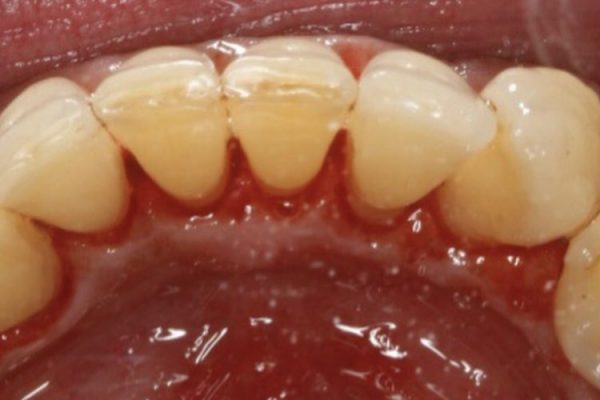

- Remove staining and discolouration caused by smoking or by drinking drinks such as red wine, tea and coffee etc

- Thoroughly remove dental plaque

- Restore white teeth

Before and After Photos